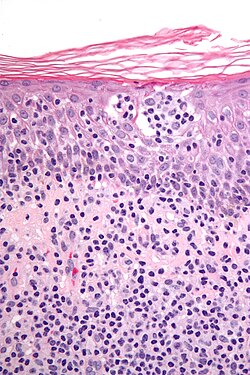

| Interface | inflammation at DE junction | -vacuolar (minimal) -lichenoid (band-like) |

-erythema multiforme, SLE -lichen planus |

[[Image:Vacuolar interface dermatitis - high mag.jpg|thumb|150px|VID (WC) |

- Vacuolar interface dermatitis (lymphocytic inflammation at the dermal-epidermal junction).

- +/-Loss of rete ridges.